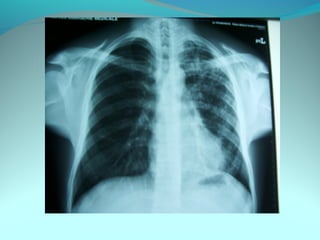

Multiple clartés arrondies de 3cm de diam dessinées au compat

entourées de parois epaisses de 5mm d’epaisseur siegeant dans la ½ sup

du poumon droit correspondant a des billes de ( ou materiel de

comblement de pneumo plastie )

Par ailleurs la ½ inf du poumon est le siege de la superposition de 2

images mixtes hydro-aérique de 8cm de diam effaçant la coupole droite

comblant les 2CDS costodiaph et cardiophrenique

On note attraction de la trachée vers laD

DIAGNOSTIC:

suppuration pulmonaire sur sequelle de pneumoplastie

Dystrophie bulleuse surinfectée sur séquelle de pneumoplastie